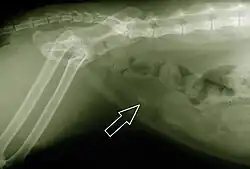

Radiografia evidenciando a existência de um cálculo na bexiga de um gato. A mancha mais clara, na ponta da seta, indica a presença de calcificação no interior do órgão em questão

A síndrome urológica felina consiste num conjunto de problemas que surgem nos felinos com o avanço da idade. O animal afetado apresenta problemas inflamatórios no sistema urinário, dentre os quais destacam-se a cistite, uremia e formação de cálculos renais e na bexiga.[179]

O principal sintoma consiste na dificuldade e dor ao urinar; algumas vezes nota-se a presença de sangue na urina. As causas dessa doença estão ligadas à alimentação do animal, além de fatores genéticos que implicam uma predisposição à sua ocorrência. O tratamento consiste na aplicação de medicamentos contra as dores e a infecção, além de um rigoroso controle na dieta do animal. Deve ser oferecida água limpa em abundância e rações que não tenham acidificantes em sua formulação, ou apresentem elevados índices de magnésio.[180]

Com uma alimentação adequada, há uma considerável diminuição da probabilidade de formação de cálculos no sistema urinário. Existem no mercado diversas rações balanceadas para diferentes tipos de gatos, variando de acordo com diversos elementos, como a raça do animal, sua idade, sexo, se é castrado ou não. É até mesmo possível encontrar rações específicas para gatos portadores da síndrome urológica felina, capazes de reduzir o pH urinário e melhorar o funcionamento dos rins, auxiliando na dissolução dos cálculos existentes e prevenindo a formação de novas calcificações.[181]